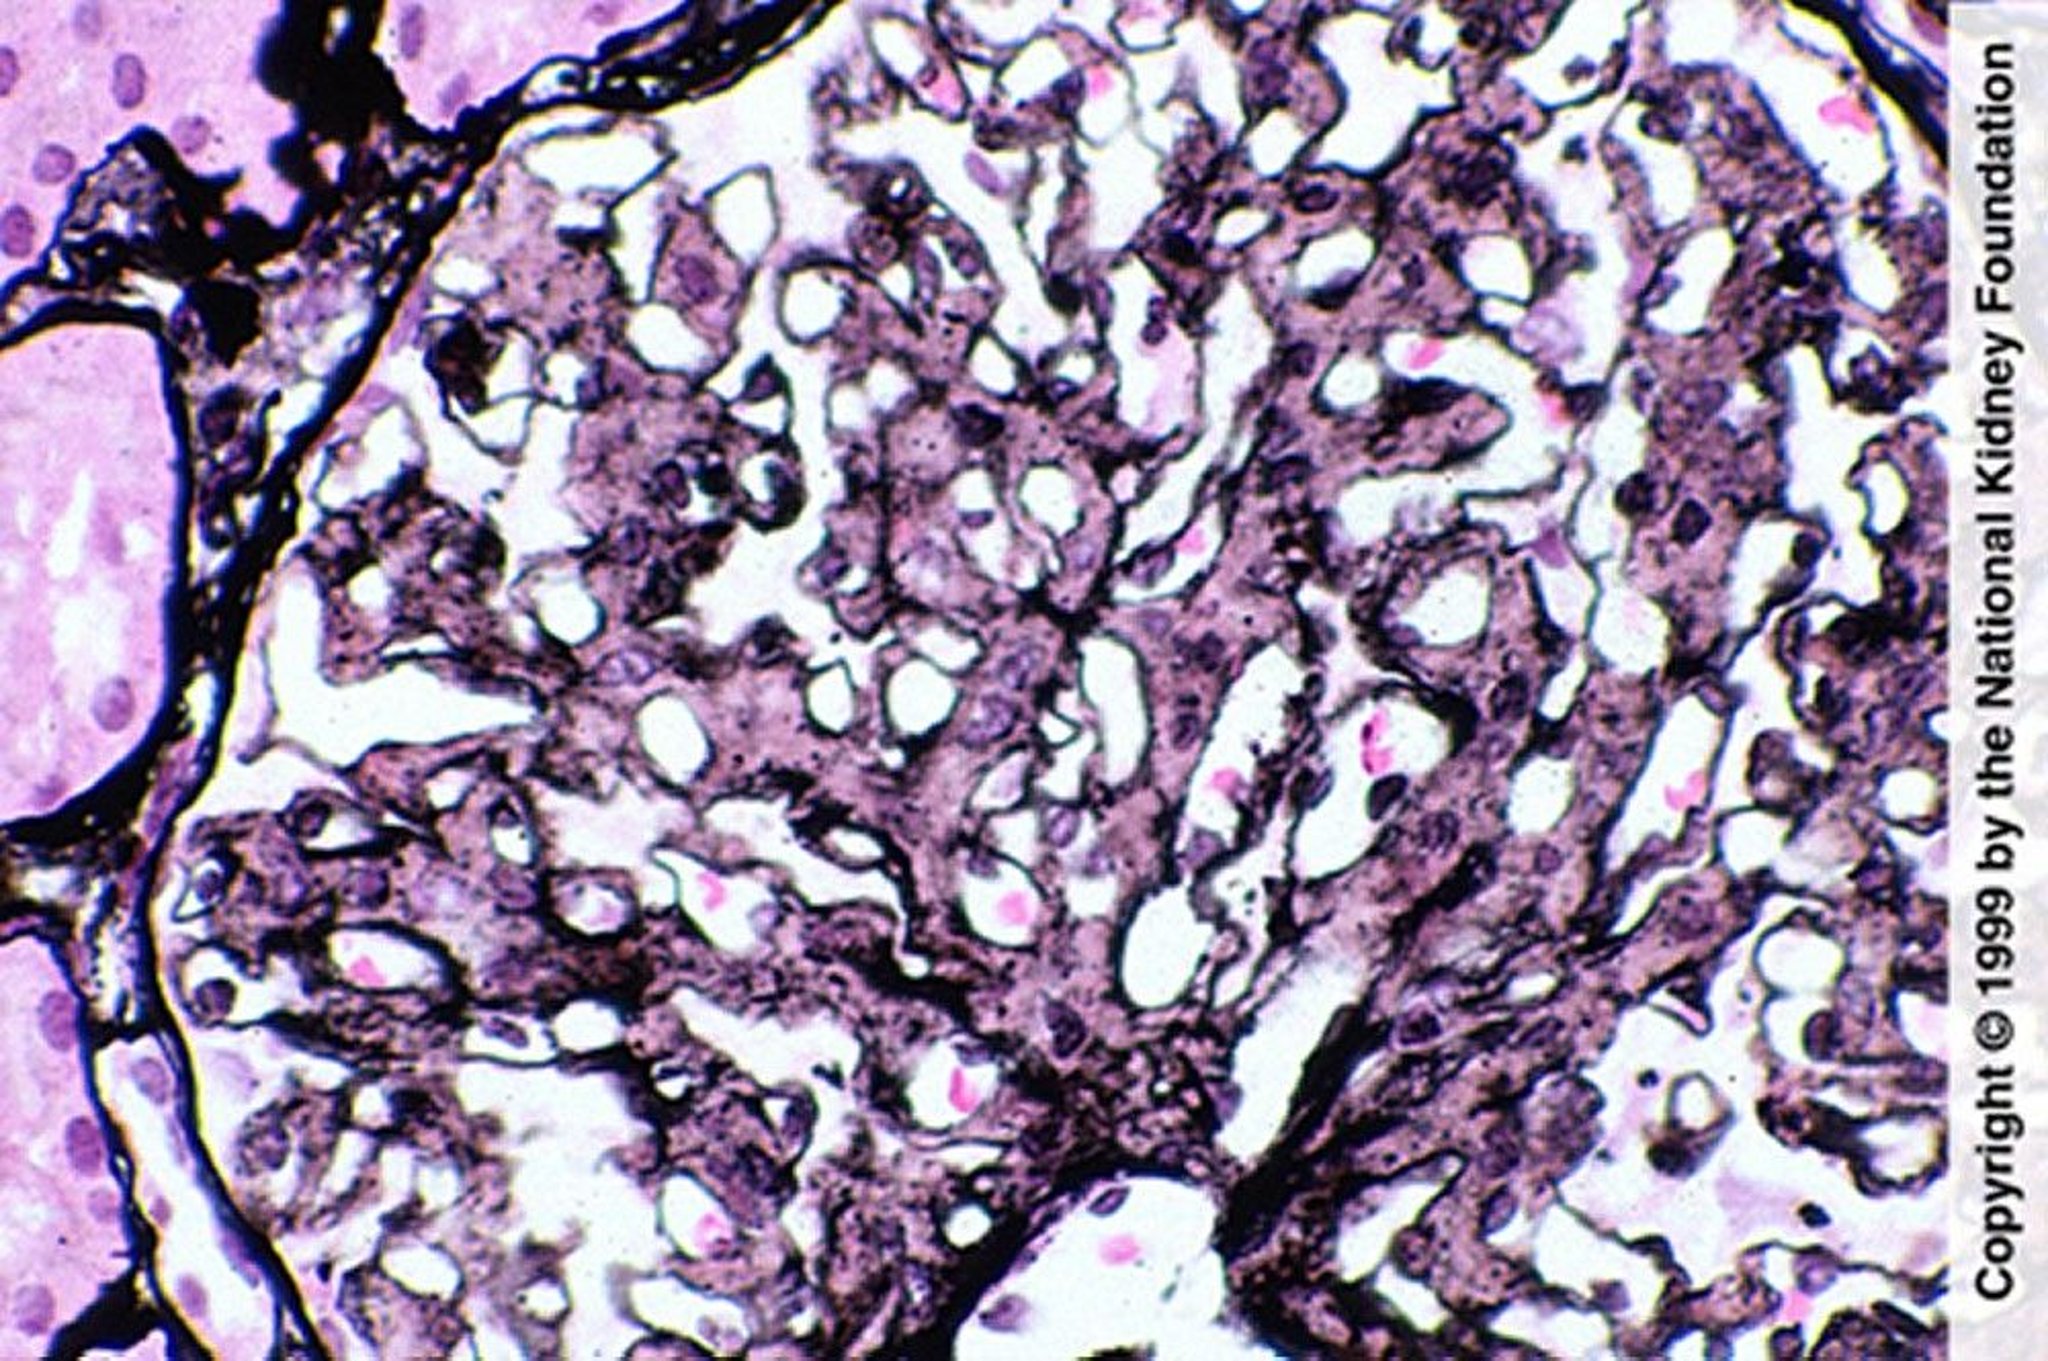

Fibrillary Glomerulopathy (Mesangial Proliferation)

Mesangial proliferation is suggestive of fibrillary glomerulopathy; however, the diagnosis requires negative Congo red stain, IgG staining by immunofluorescence, and demonstration of fibril on electron microscopy (Jones silver stain, ×400).

Image provided by Agnes Fogo, MD, and the American Journal of Kidney Diseases' Atlas of Renal Pathology (see www.ajkd.org).